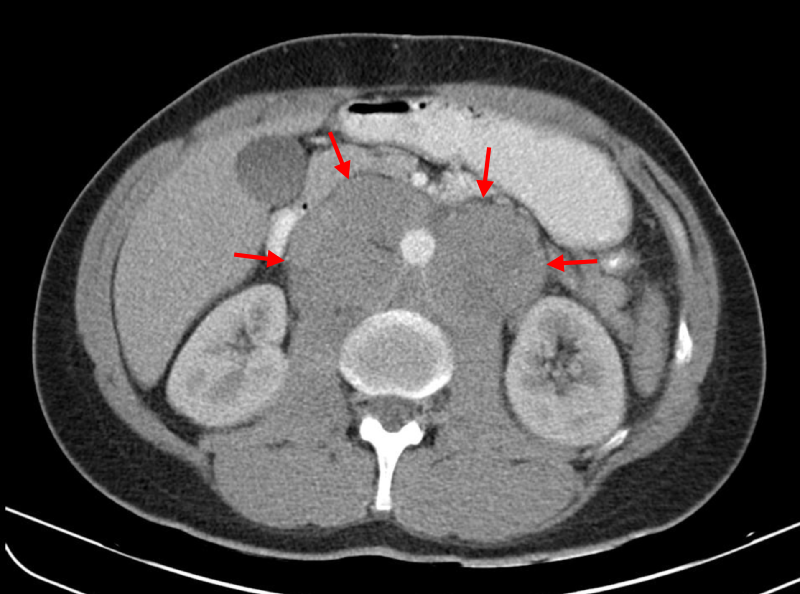

- Typically presents as an extranodal mass

- The abdomen is typically involved

DLBCL typically presents as an extranodal tumor or an expanding lymph node in late adulthood.